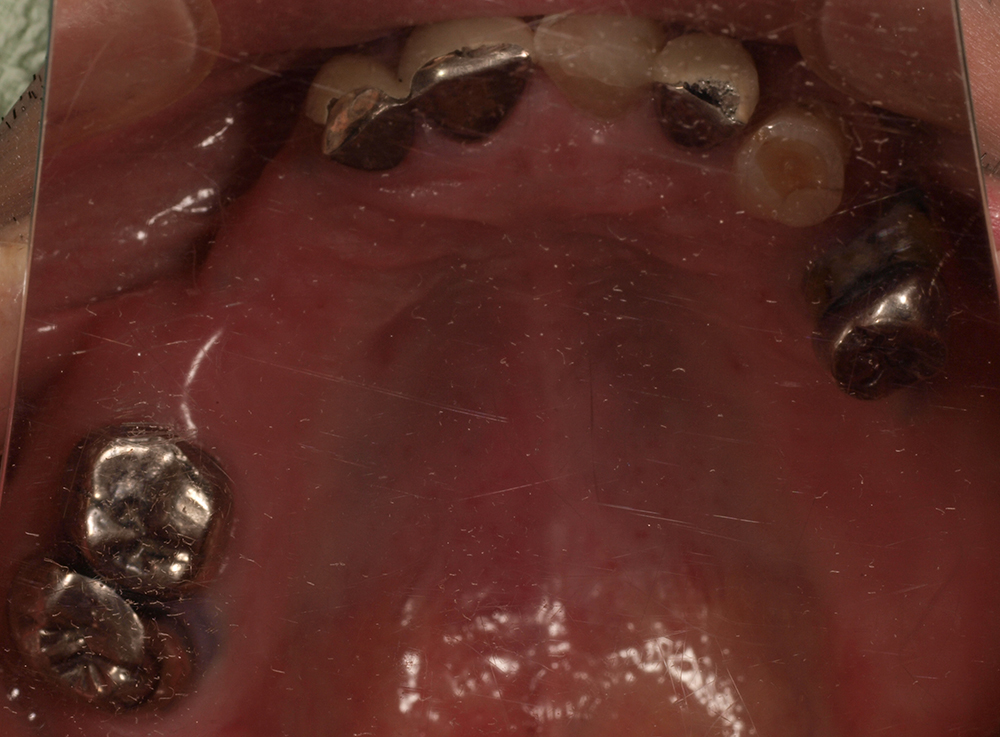

55歳 男性

- 主訴

- 前歯でしか咬めなく、食事を採るのに非常に困難で辛い

- 処置内容

- 上顎6本、下顎3本

- 治療費用

- 上顎:約230万(税込)下顎:約120万(税込)

- 治療期間

- 上顎:1年(仮歯まで8か月)下顎:8か月(仮歯まで5か月)

- リスク

- 上部構造物、仮歯の破折、術後の腫れ(3日)、人工歯根脱落リスクがあります